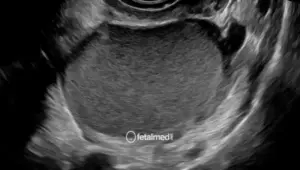

Ecocardiografia Fetal

Ecocardiografia fetal com Doppler colorido para avaliação detalhada do coração do bebê. Diagnóstico de cardiopatias congênitas em Curitiba.

A ecocardiografia fetal é um exame de ultrassom especializado que avalia detalhadamente o coração do bebê ainda durante a gestação. Utilizando tecnologia de Doppler colorido, permite identificar cardiopatias congênitas com alta precisão diagnóstica.